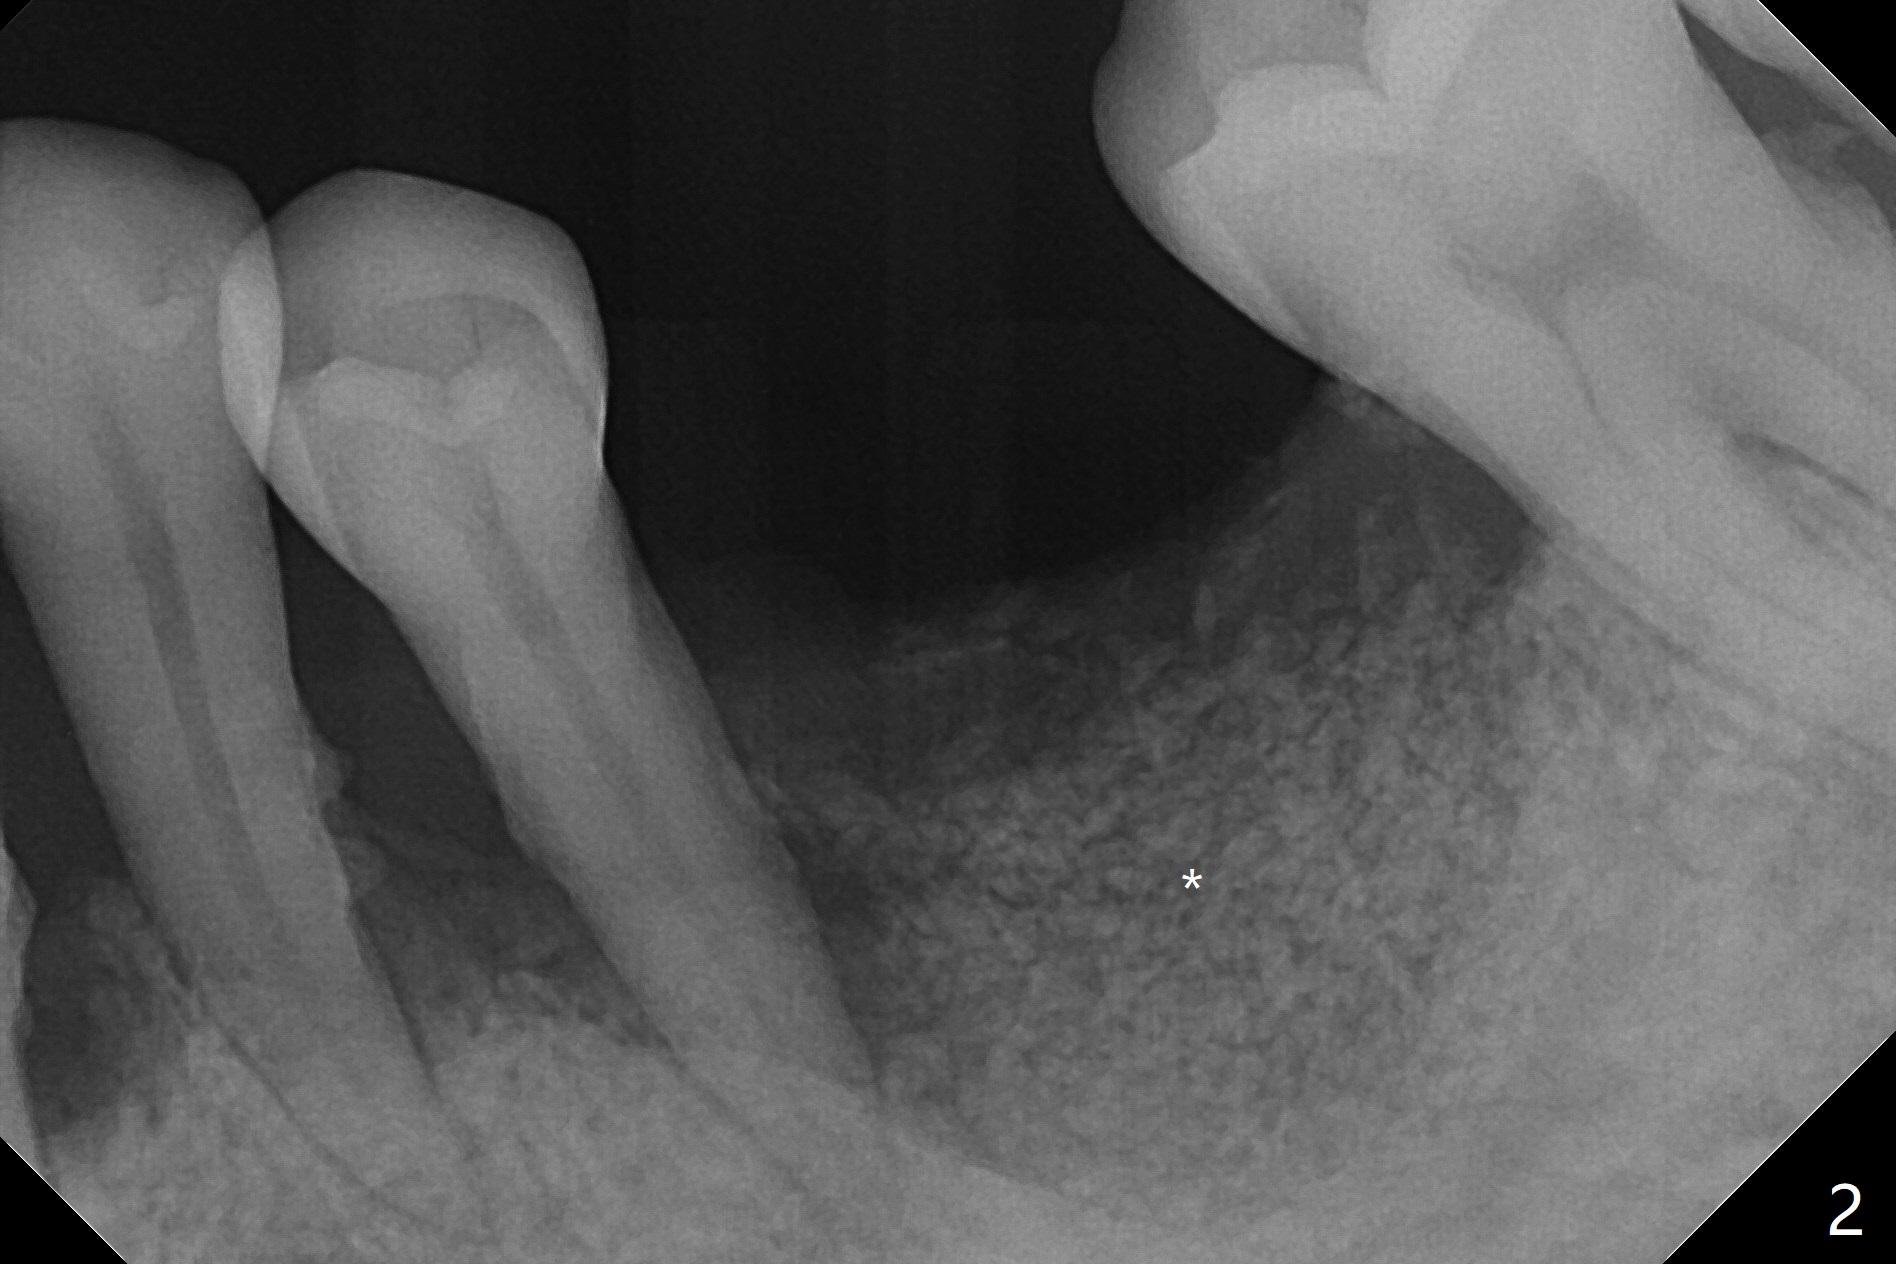

A 38-year-old man requests removal of the tooth #19 with mobility (Fig.1). With block anesthesia (more profound anesthesia than infiltration), SRP, extraction and socket preservation are conducted (Fig.2).